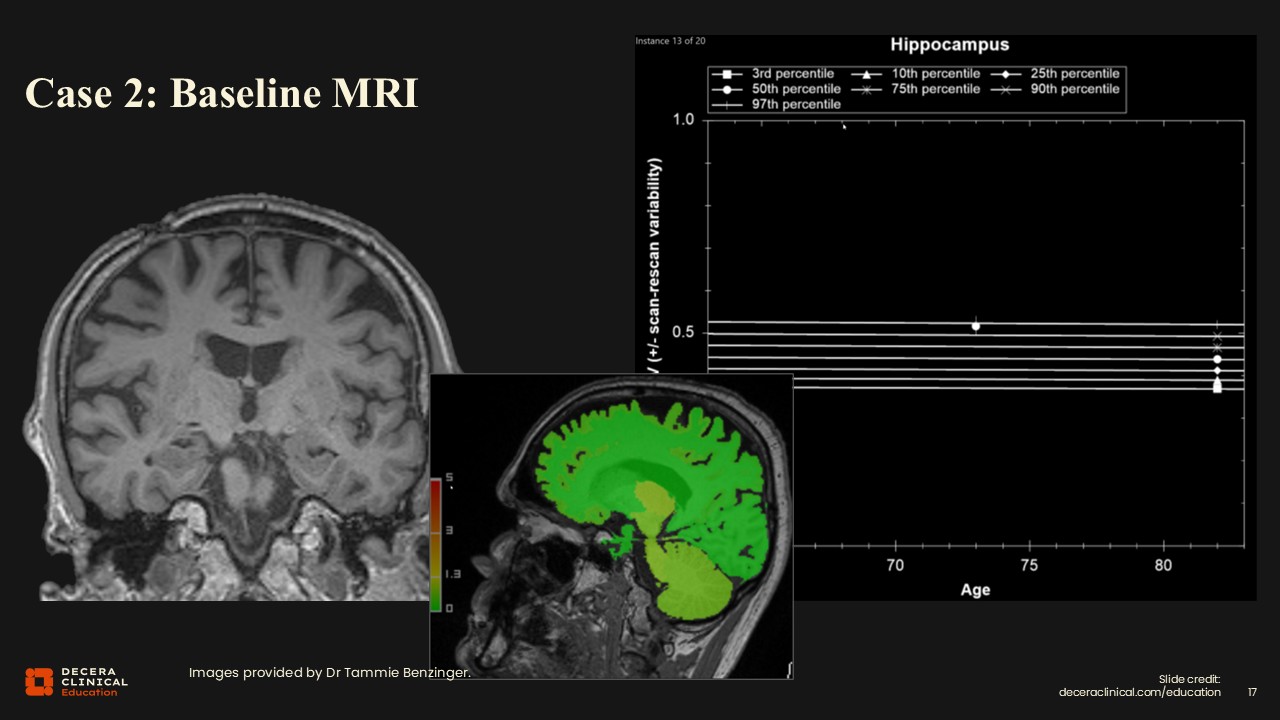

Case 2: Baseline Imaging

Brain volumetrics are normal, and in fact, hippocampal volumes are actually better than normal with no atrophy.

Case 2: Baseline MRI

This is another case in which the brain MRI appears almost normal; FLAIR, SWI, and GRE/T2* all look very good. An astute observer might note a prior burr hole, prompting clarification regarding the reason for his previous craniotomy.